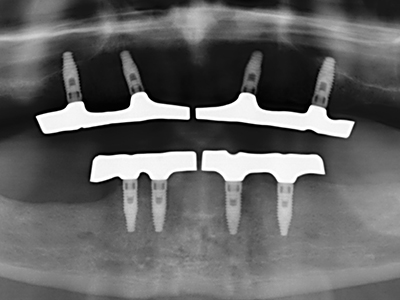

La piezochirurgia presenta altri vantaggi per quanto riguarda la raccolta di blocchi ossei. Oltre all'elevata precisione dell'osteotomia appena descritta, l'utilizzo di puntine per sega molto sottili permette di minimizzare in maniera significativa la perdita di materiale. È molto probabile che si verifichi una maggiore perdita di materiale durante la raccolta utilizzando puntine di strumenti più spessi, in particolare delle frese Lindemann (Lakshmiganthan, Gokulanathan et al. 2012). La separazione basale, necessaria in particolare per i trapianti di blocchi nella zona retromolare, viene semplificata grazie a seghe specificatamente progettate di forma rettangolare; di conseguenza la piezochirurgia è considerata una procedura precisa, semplice e sicura per la raccolta di blocchi di osso nella zona retromolare (Happe 2007) (figg. 1-12).